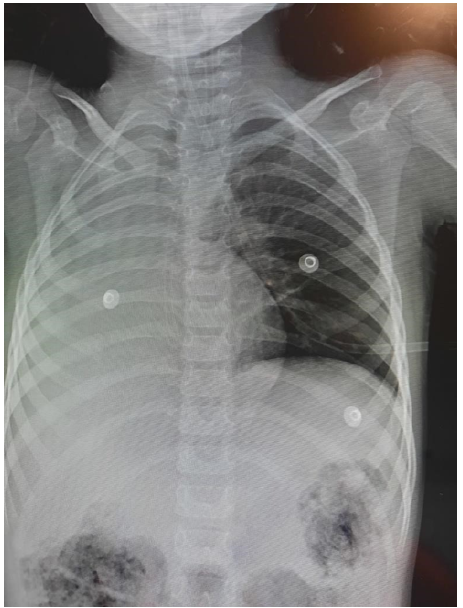

Case Report

Lidocaine Poisoning in a Pediatric Patient, Regarding a Case

Ibeth Georgina Cedillo Velásquez, David Nicolás Mendoza Irías, Scarlett Nabila Rodríguez Flores, Gennar Nohelia Vallejo Padilla, Karen Melissa Lainez Maldonado, María Alejandra Orellana Rivera, Oscar Fawed Ortega Reyes. 6(3): 67-70.